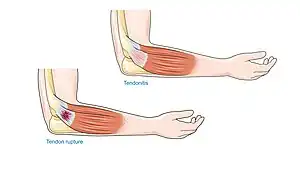

Achilles tendinopathy

Achilles tendinopathy and peritendonitis